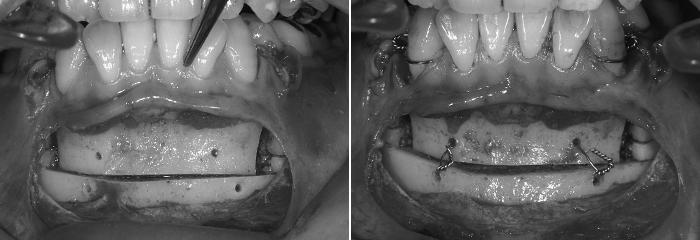

13. 骨を固定します

口ごぼ改善のための、見た目とかみ合わせが理想の形に整ったら、骨を固定します。固定材料には、溶けるプレート、チタン製のプレート、ステンレス製のワイヤーがあります。どれを使うかは、手術中の骨の安定感や調整の多い、少ないなど状況に応じて使い分けます。

10. 後ろに下げた骨を固定します

見た目の調整が終わり、かみ合わせも良くなったら、その位置に下あごの骨を固定します。後ろに下げた上のあごの位置に合わせます。

固定する材料は、チタン製のプレート、骨接合用ステンレス製のワイヤー(矯正用のワイヤーとは違います。)、溶けるプレートがあります。どの固定材料を使うかは、上と下のかみ合わせ具合や、お鼻やあご先とのバランス、手術中の骨の安定感や調整の程度など状況に応じて使い分けます。

11. 仮止めします

上下のあごを手術中だけ固定して、安定させます。

予定の位置に移動した骨を戻して、最もきれいな見た目の位置と噛み合わせの位置で上下のあご、歯と歯の当り方を最終確認します。

顎関節、嚙み合わせ、見た目のバランスを整えて、あご関節の受け皿、あご関節のあたま、かみ合わせ、見た目のバランスを調和させます。中心位と中心咬合位をぴったりと合わせるために顎間固定をした状態であご先を手で動かして、関節の頭を関節の受け皿部分の最も後ろで最も上の位置に誘導します。(カンファ―クリニックでは、最終的な顎間固定はおこないませんから、手術後から食事ができます)